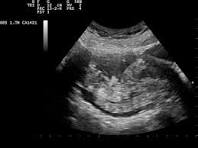

Real-time imaging is necessary to spot abnormalities and evaluate tissues and organ health during check-ups. Hence, a reliable and precise ultrasound is necessary for patients seeking medical advice and diagnosis.

Pearl Hospital provides precise and reliable ultrasound services. The Ultrasound Preliminary reports allow clinical staff to know of critical findings before the technician leaves the building and a final report from the radiologist follows shortly after.

At Pearl Hospital, all ultrasounds are done by a Consultant Radiologist. The client gets very high-resolution images due to the state-of-the-art ultrasound machine used.